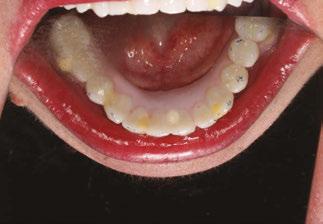

Case report

A 49-year-old female patient presented with the chief complaint of her inabil ity to wear her current full maxillary and mandibular dentures due to a significant gagging reflex, indicating the dentures were delivered 2 years previously. She also expressed dissatisfaction with the current esthetics of the prosthesis and her smile. The patient’s general dentist had referred her for an implant consul tation. Her medical history was reviewed, and no significant health issues were disclosed.

A CBCT scan was taken and panoramic views of the maxilla and mandible evaluated (Figure 3). Bilateral pneumatization of the maxillary sinus was noted, but adequate bone height was present between the premolars for implant placement to support an All-on-X hybrid prosthesis. In the mandibular arch, sufficient height was available between the mental foramen bilaterally and over the inferior alveolar nerve for implant placement to also sup port an All-on-X fixed hybrid prosthesis. A discussion was held with the patient that implants could be placed in both arches that would allow restoration with fixed prosthetics. Should sufficient insertion torque be achieved at the time of implant placement, a screw-retained hybrid provisional prosthesis would be placed and worn for several months during healing after which a final prosthesis would be fabricated. The patient would also be able to do a “trial-run” of the esthetics with the provisional prosthesis, with any requested modifications made when the final prosthesis was designed and fabricated. The treatment plan included six implants in each arch to support the planned hybrid prosthe ses. The patient was informed that reduction of the crestal bone would be required to achieve a flat ridge for adaptation of the prosthesis to the ridge as well as to provide adequate interarch space for the final prosthesis. The patient accepted the treatment plan. An intraoral scan of the arches was performed with Medit i500 (Medit Corp, Seoul, Korea) as well as the current complete arch maxillary and mandibular dentures (Figure 4). The patient was dismissed and scheduled for the surgical appointment.